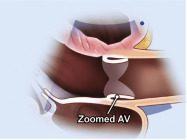

| 2.3. Mặt cắt trục dài cạnh ức phóng đại van động mạch chủ

Cửa sổ siêu âm cạnh ức

Mặt cắt trục dài cạnh ức Đặt hộp phóng đại vào vị trí van động mạch chủ, đường ra thất trái, động mạch chủ lên Chùm siêu âm đặt vuông góc với cấu trúc và có thể đặt đầu dò lên các khoang liên sườn cao hơn nếu cần. |

Van động mạch chủ (AV) | |||||